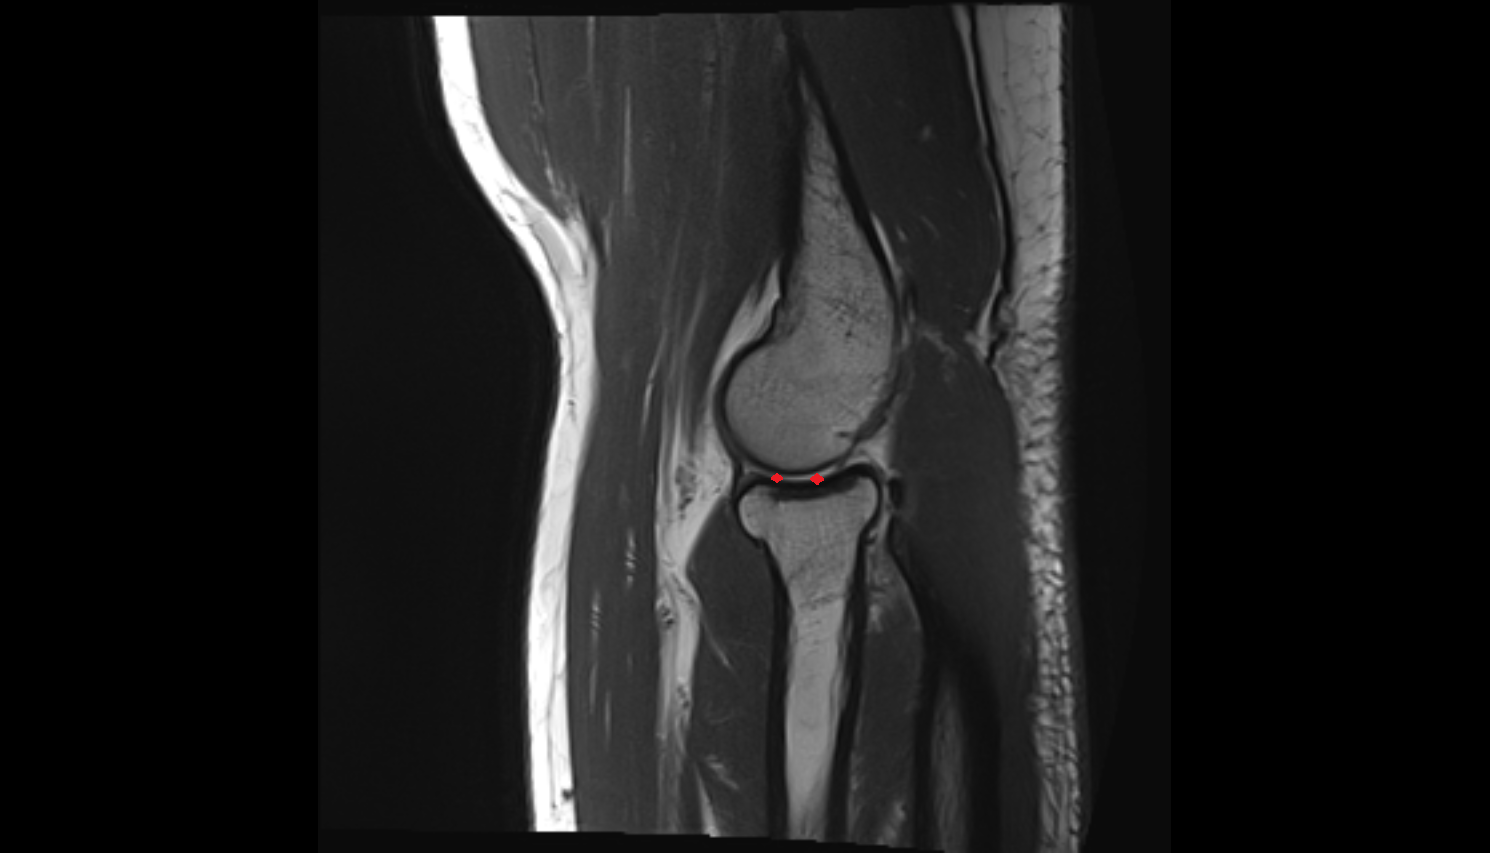

- Medial meniscus

- Lateral meniscus

- Knee Joint